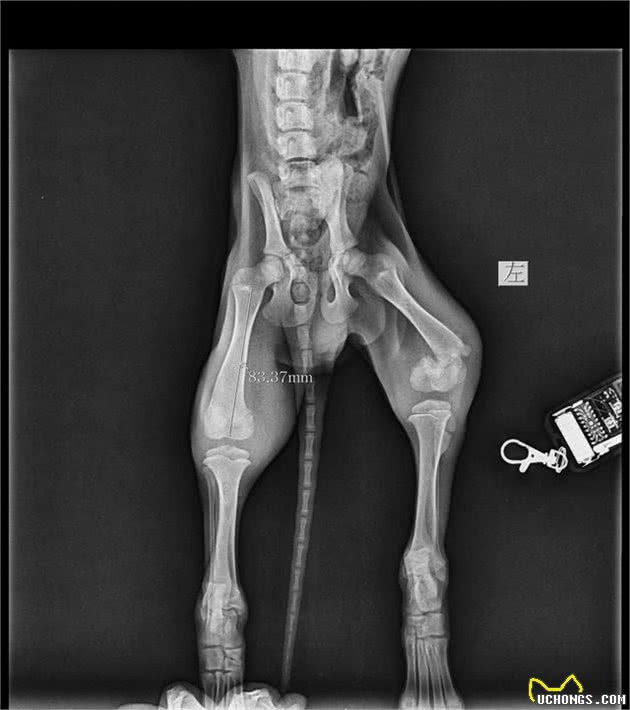

临床的体格检查发现左后腿肿胀,触碰疼痛,没法着地,站立以及走路没法着力,于是进行进一步的影象学检查。X-Ray是诊断以及评价骨骼的最好办法,靠触诊也许会发现存在骨折,可是整体的骨头是非常难评价的。所以对于这类骨科的病例,通常需要触诊后,进一步针对性的部位进行x-ray拍摄,拍摄的影象即可供判读参考。

X-Ray后肢正位片

大家能够发现这个拉布拉多犬的左后腿明显的存在骨折,以及外周组织的肿胀。对于这样的骨折,做外固定是能够,可是需要承担很大的风险,为什么?因为狗狗不像人,伤筋动骨一百天,虽然幼犬还在生长期,断掉的骨头长起来会很快,可是狗狗会真的那么听话,让他躺三个月就躺三个月吗?所以说外固定最大的风险就是狗狗活泼好动,断掉的骨头没办法很好的吻合,会造成长短腿,长歪等的风险,会永久的造成狗狗走路跛行(十分明显的跛行)。

X-RAY左后腿的侧位片

在所有指标都正常的情况下能够进行镇静,镇静以后需要给手术部位(骨折部位)重新摆位,拍摄完整的影象图,因为在门诊的检查中,宠物常常因为疼痛,会在拍摄时竭力的抗拒,会导致摆位不正,恍惚,不整齐等瑕疵,毕竟宠物拍摄X-RAY不像人一样,医生让你怎么摆就怎么摆。镇静后的拍摄手术部位能够保证摄片的质量,也主要是为了更好的测量骨头的长度以及直径,进而能够选择合适的髓内针。